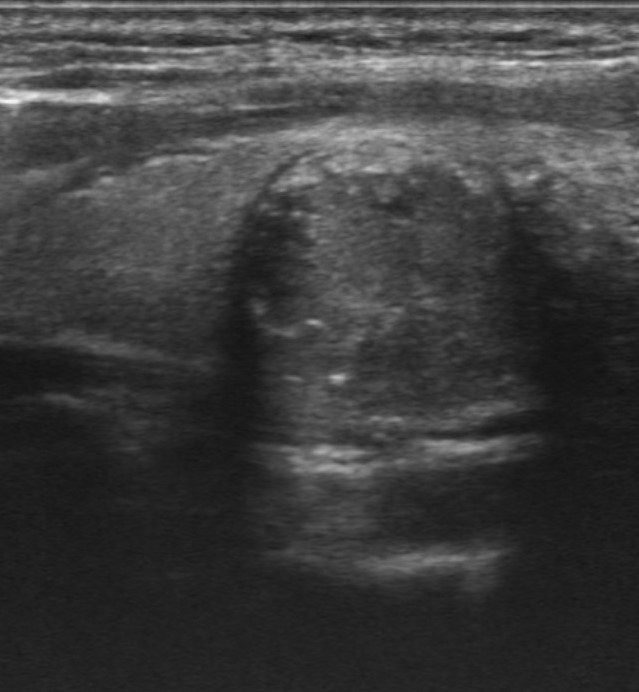

Hallazgos ecográficos

Nódulo de 16,9×15,1 mm, sólido, hipoecoico, de bordes mal definidos, más alto que ancho y con microfocos ecogénicos y calcificación periférica en anillo. Se clasifica como TIRADS 5, altamente sospechoso de malignidad e indicativo de PAAF al superar los 10 mm.